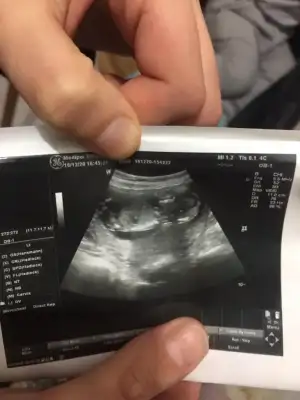

Seninkini at bakayım birde ben göreyim 🤭 ben aslında 12. Haftada gittiğimde kız olduğunu fark ettim pipi gibi birşey yoktu assagi doğru eyik gözükuyordu🤗

Bizimkide bu su pipi mi kordon mu anlamadım 😅 insallah kordondur yeni oluşan pipi bu kadar büyük olur mu acaba 😅